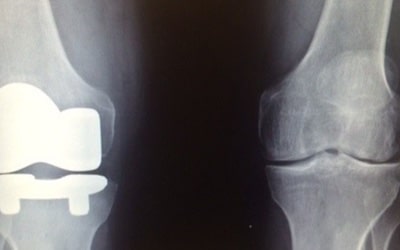

Joint Replacement

This is the removal of an arthritic or damaged joint, replacing it with an artificial joint.

- Joint replacement of the hip and knee